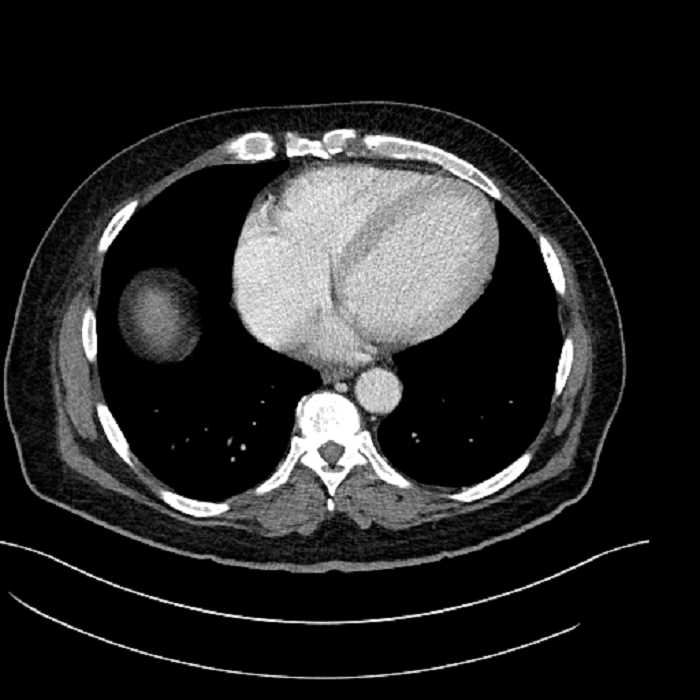

• Lower chest

• Mild cardiomegaly

• Mild dependent atelectasis

Acute sigmoid diverticulitis complicated by a small contained perforation and a large abscess in the right hepatic lobe. Additional small subcapsular abscesses along the anterior margin of the left hepatic lobe.

Hepatic abscess showing the double target sign with low density internally surrounded by a thin inner enhancing rim (red arrow) and ill-defined outer low density rim (yellow arrow). Blue arrow indicates an internal septation. Red arrows: additional smaller subcapsular abscesses. Red arrow: focal contained perforation associated with diverticulitis.